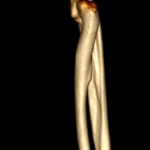

2歳の柴犬ちゃんが、生まれてすぐに痛めた肘に徐々に痛みが出てきたとのことで、主治医から診察と必要があれば手術をして欲しいと連絡がありました。CTでは橈骨頭が外側に脱臼して変位していました。また回転性の変形を伴っています。同時に尺骨にも湾曲が認められています。このような変形矯正には3Dプリンターで模擬手術を行いあらかじめシミュレーション手術をしておくと時間の短縮と正確な変形矯正が可能となります。このようなテクノロジーを動物医療にもどんどん取り入れていきたいと思います。また、骨きり部位にはPRFと自家海綿骨移植を行い治癒促進を期待します。